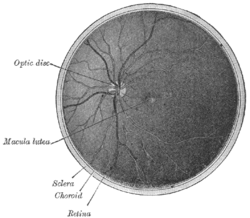

The optic disc or optic nerve head is the point of exit for ganglion cell axons leaving the eye. Because there are no rods or cones overlying the optic disc, it corresponds to a small physiological blind spot in each eye.

The ganglion cell axons form the optic nerve after they leave the eye. The optic disc represents the beginning of the optic nerve and is the point where the axons of retinal ganglion cells come together. The optic disc is also the entry point for the major blood vessels that supply the retina.[1] The optic disc in a normal human eye carries from 1-1.2 million neurons from the eye towards the brain.

The optic disc is placed 3 to 4 mm to the nasal side of the fovea. It is a vertical oval, with average dimensions of 1.76mm horizontally by 1.92mm vertically.[2] There is a central depression, of variable size, called the optic cup.